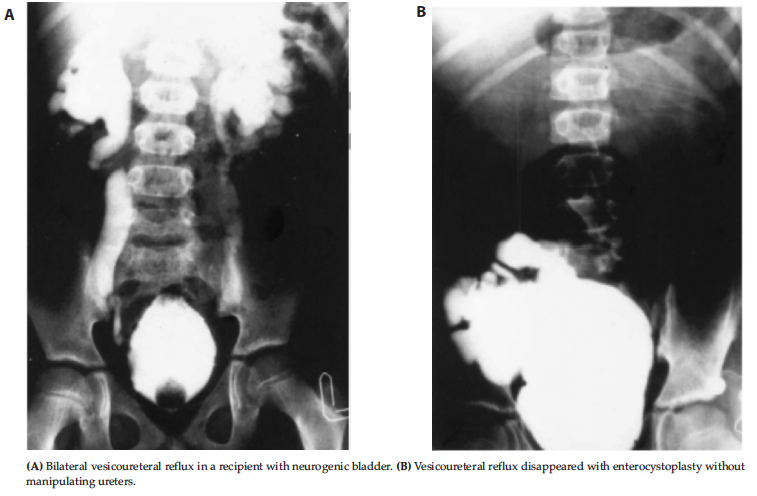

Management of Neurogenic Bladder in Kidney Transplant

We previously compared bladder augmentation before and after kidney

transplant.11 One of the important diseases leading to ESRD is significant

bladder dysfunction. Among the different kinds of neurogenic bladders that cause

ESRD, a hypertonic bladder with dyssynergic sphincter is the most common type.

Bladder augmentation has grown in popularity as a treatment for neurogenic

bladder in renal transplant patients. Presently, ileocystoplasty is the common

procedure for augmentation enterocystoplasty. If a recipient with ESRD has

gross vesicoureteral reflux, usually there is no need to do augmentation

enterocystoplasty before renal transplant because there is a pop-off mechanism

(Figure 7). Augmentation cystoplasties in selected patients before or after

transplant are both safe and yield accepted morbidity.

In our center, we follow these steps when a patient with neurogenic bladder and ESRD is referred to us. If the patient has gross vesicoureteral reflux, kidney transplant is performed without doing enterocystoplasty and the patient is followed closely. If the patient has chronic renal failure and is on dialysis, kidney transplant is performed and the patient is followed. If an indication such as hydronephrosis in the transplanted kidney is shown, augmentation cystoplasty is performed. However, if the patient already has an augmented bladder, we will transplant the kidney on the augmented bladder.

Figure 7. Bladder Augmentation